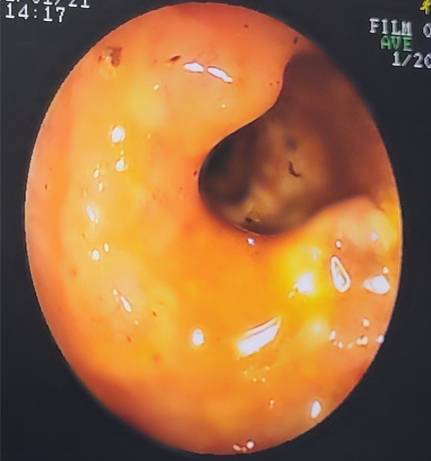

發現結腸黏膜有環狀增生,外形不規則,緊接著就採樣經組織病理醫師診斷為直腸腺癌。